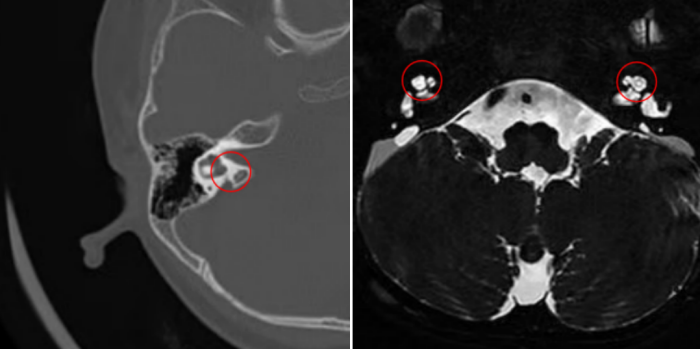

乐乐出生即被确诊为“先天性重度感音神经性聋”,佩戴高端助听器一年多,语言发育仍无进展。父母慕名找到了长沙市中心医院冯永教授。经过详细问诊与系统评估,冯永教授判断,乐乐残存的听神经尚有潜力,而“人工耳蜗植入”可能是唯一的解决方案。然而,术前的影像学检查揭示了一个更复杂的挑战:乐乐患有典型的Mondini畸形(耳蜗仅发育1.5圈,仅为正常人的一半)合并大前庭导水管综合征。这种复杂的内耳结构异常,使得人工耳蜗植入手术的难度和风险呈几何级数上升。

耳蜗Mondini畸形,耳蜗仅为正常人的一半

冯永教授介绍,正常耳蜗形似蜗牛壳,是声音信号转化为神经信号的核心。而乐乐的耳蜗不仅结构不完整,其异常扩大的前庭导水管还像一个随时可能“决堤”的通道,术中极易发生脑脊液“井喷”,即内淋巴液大量涌出,这是耳科手术中最凶险的情况之一。此外,电极如何精准植入发育不全的耳蜗、能否有效刺激听神经,都是摆在团队面前的难题。